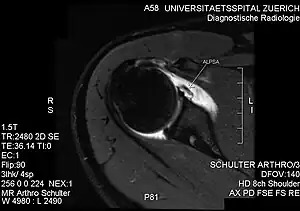

PD-weighted MRI with fat saturation of the shoulder showing an ALPSA lesion